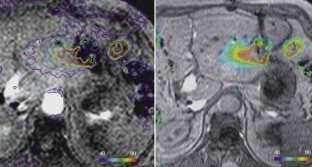

Im interdisziplinären Konsens wurden 182 Patienten (Lebertumoren: 131, andere Tumoren—Knochen, Lunge, weitere Tumoren: 51) mit 1–6 Applikatoren behandelt. Die Interventionen erfolgten in Kombination verschiedener Modalitäten (CT/MRT; CT/US) oder ausschließlich im geschlossenen MRT (1,5 T) mit direkt postinterventioneller MRT-Kontrolle.

Bei Lebertumoren wurde eine Ablationsrate von insgesamt 90,9% erzielt, die MRT erwies sich als optimale Methode zur Prozesssteuerung und direkten postinterventionellen Kontrolle. Die Komplikationsrate („major events“) betrug 5,4%. Bei nichthepatischen Tumoren ergab sich eine hohe technische Erfolgsrate mit organabhängig unterschiedlichem klinischem Erfolg.

Die Laserablation mit neuen Techniken ist ein sicheres und nebenwirkungsarmes Verfahren zur Behandlung von Leber- und anderen Tumoren bis zu einer Größe von 5 cm. Die MRT hat sich für die exakte multiplanare Abbildung des Tumors, die Prozesssteuerung und die Erfolgskontrolle der Laserablation bewährt.

Laser ablation was performed in 182 patients (liver tumors: 131, non hepatic tumors—bone, lung, others: 51) after interdisciplinary consensus was obtained. The procedure was done using a combination of imaging modalities (CT/MRI, CT/US) or only closed high field MRI (1.5 T). All patients received an MRI-scan immediately after laser ablation.

The treatment of tumors of the liver and other organs up to 5 cm by laser ablation was a safe procedure with a low rate of complications and side effects. Image guidance by MRI is advantageous for precise tumor visualization in all dimensions, therapy monitoring, and control of laser ablation results.

Abb. 5

Abb. 6